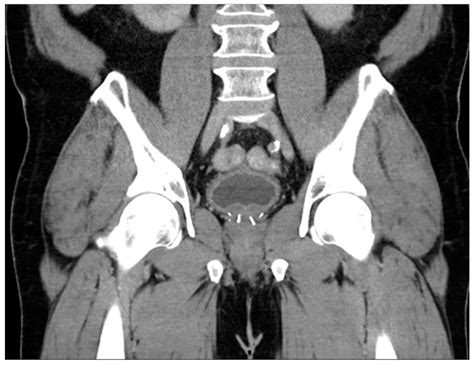

To accurately determine if an individual’s prostate falls within a normal prostate volume range, medical professionals employ specific diagnostic tools. These imaging techniques provide precise measurements that are far more reliable than a digital rectal exam alone. The common methods include:

Magnetic Resonance Imaging (MRI) Provides highly detailed cross-sectional images, often used when high accuracy is required for biopsies or surgical planning.